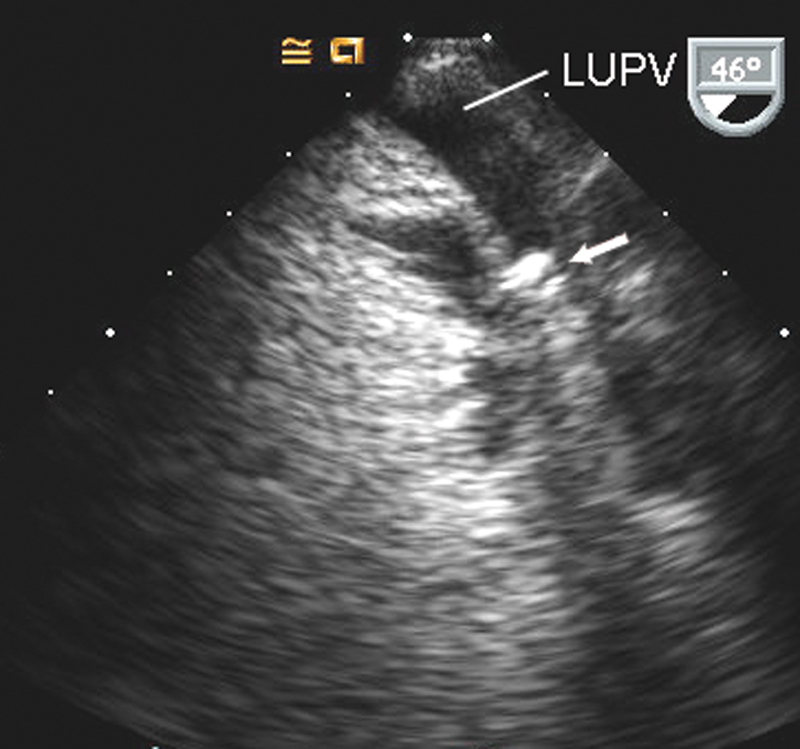

فحوصات تشخيصية لبعض امراض القلب والشرايين التاجية